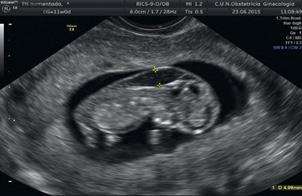

Certeza: La ecografía transvaginal es la prueba confirmatoria de embarazo. A las 4.5 semanas, se observa saco gestacional; a las 5 semanas, se encuentra embrión, y a las 6 semanas es posible auscultar los latidos cardiacos fetales con el doppler . También se considera la percepción de movimientos fetales por parte del médico.

Figura 11. Ecografía de I trimestre Examen de certeza para confirmar un embarazo eutópico y viable

En la del I trimestre (10-14 semanas), se confirman la gestación, la edad gestacional de forma más precisa midiendo la longitud craneocaudal (LCC)

(ENAM EXTRA 2021), y la vitalidad del embrión (actividad cardiaca) (ENAM EXTRA 2020)

Es considerada la ecografía más importante por 3 propósitos:

Evaluación de riesgo genético (riesgo de cromosomopatías o aneuploidías)

Evaluación morfológica (exclusión de malformaciones visibles en el 1er trimestre)

Evaluación de riesgo de preeclampsia y RCIU.